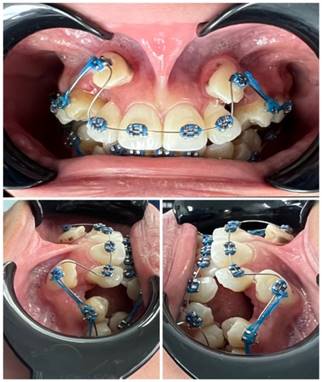

Se presenta el caso de una paciente femenina de 20 años que se encontraba en tratamiento ortodóntico hacia aproximadamente 1 mes. La paciente no reportó antecedentes patológicos de relevancia. Al practicar el examen estomatológico se observó un frenillo labial superior de implantación larga (Tipo II), situado encima de los incisivos centrales superiores. A la exploración no presentaba diastema en los incisivos centrales superiores, por lo que el tratamiento se indica para una mejor movilidad labial y beneficios estéticos.

Se remitió a la paciente a las clínicas odontológicas de UNIANDES, sede Ambato, edificio Dra. Corona Gómez PhD para realizar el tratamiento de frenectomía labial superior. Una vez explicado el procedimiento a la paciente de manera verbal y escrita se programó la fecha quirúrgica (Figura 1).

Figura 1. Fotografías intraorales del paciente.

Elaboración: Los autores.